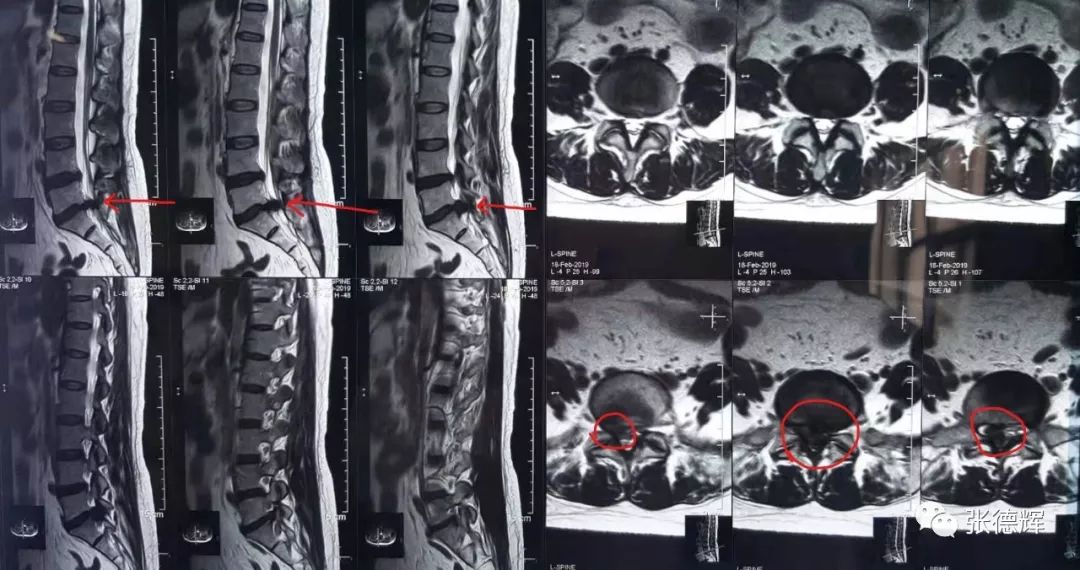

患者术前的各项影像检查

腰椎核磁及CT均提示腰5-骶1巨大椎间盘脱出,椎管占位,马尾神经受压明显

根据患者的这些临床症状及其影像学检查结果

我们判断—— 患者为“ 腰5骶1巨大椎间盘脱出 ”并有“ 马尾综合征 ”迹象